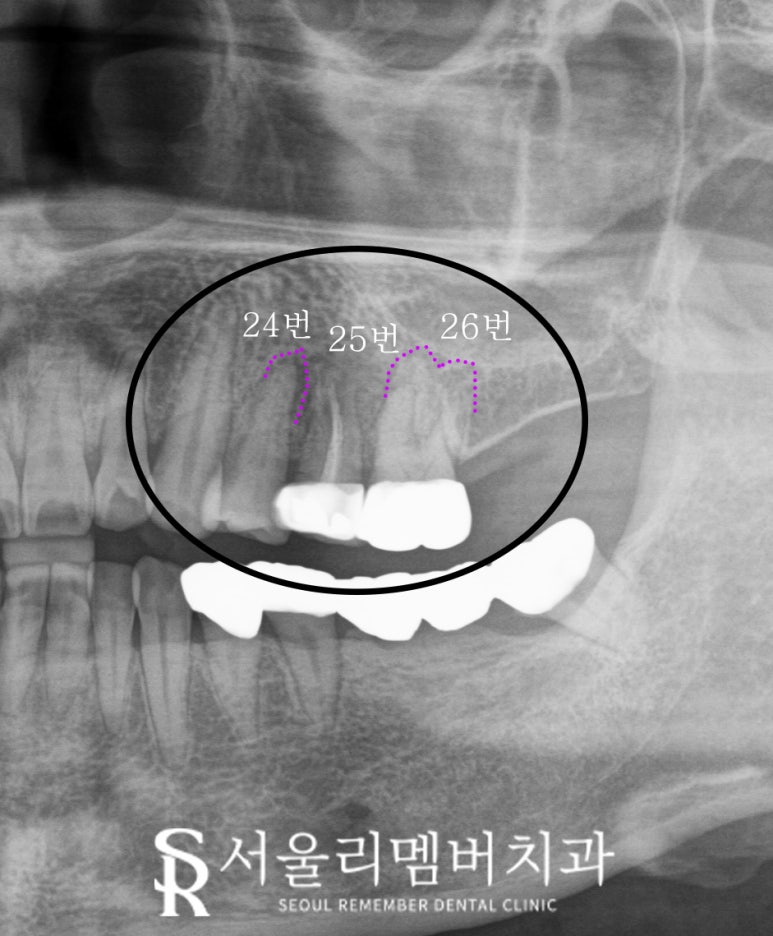

그러나 이 케이스에서는

자세히 보면 앞뒤 24, 26번 치아 뿌리 끝에

염증 소견이 보이고 있습니다.

아무래도 오른쪽 아래 어금니들이 없다 보니

식사를 할 때 주로 왼쪽을 사용하셨을 것이고

그러다 보니 저작력을 많이 받은

치아에서 문제가 생기는 것이죠.

크라운만 교체하면 되지 않을까?

싶었던 25번도

오랜 시간 강한 힘을 버티다 보니

치근이 수직으로 파절되어 있었습니다.

이렇게 뿌리에 세로로 금이 가버렸다면

이때는 발치가 불가피합니다.

봉천역 치과 에서는

근단 농양이 생긴 24, 26번은

신경치료 후 크라운을 씌워

조금 더 사용해 보기로 하였으며

치근 수직 파절 소견을 보이는

25번은 뽑고 임플란트를 하기로 했습니다.